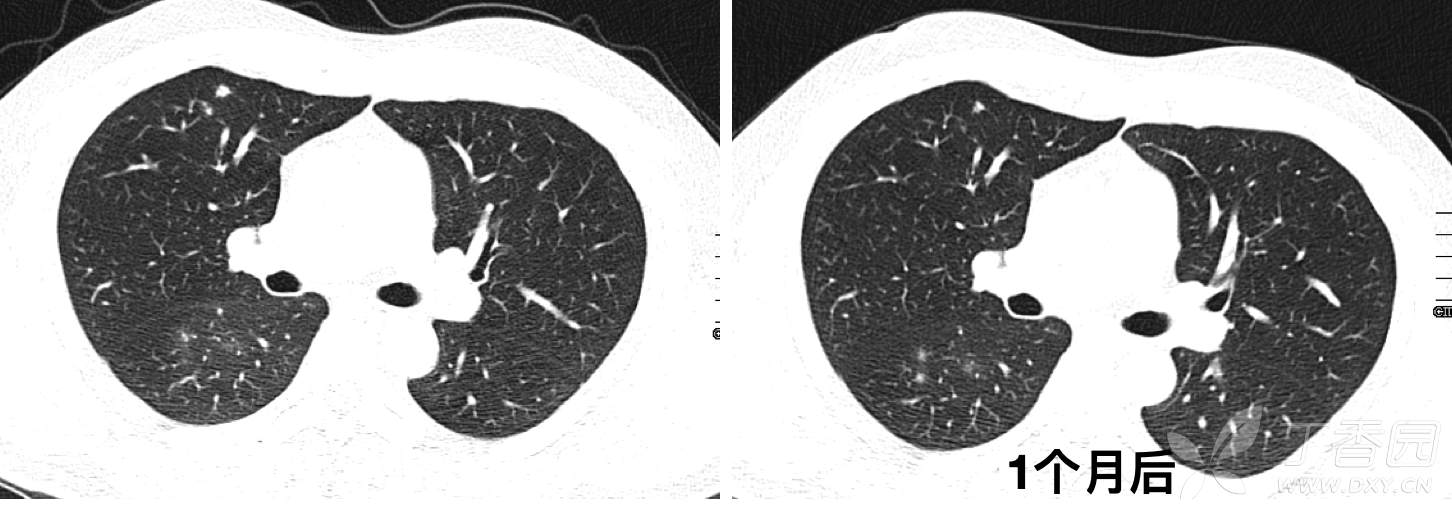

CT发现右肺多发结节影,初步诊断为肺炎,予莫西沙星口服治疗2周,1个月后复查CT如下: